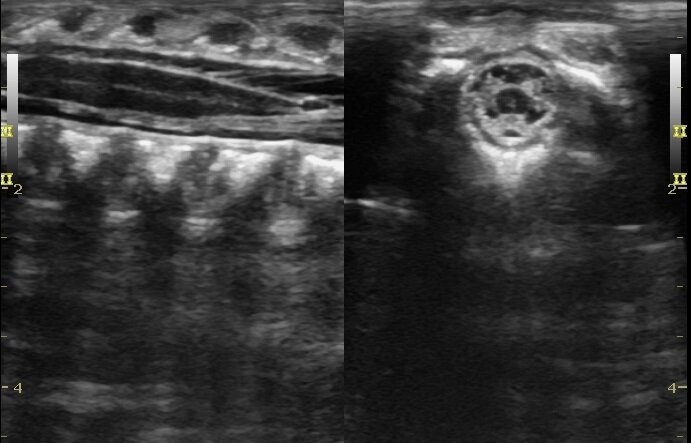

Фото результатов УЗИ шейного отдела позвоночника младенца.

На УЗИ у младенца мы видим пока ещё хрящевые ткани позвонков. Их ротации, смещения и наклоны в ту или иную сторону, если говорить про шею.

Видим именно ткань самих позвонков, и то, что они находятся в неверном расположении друг относительно друга.